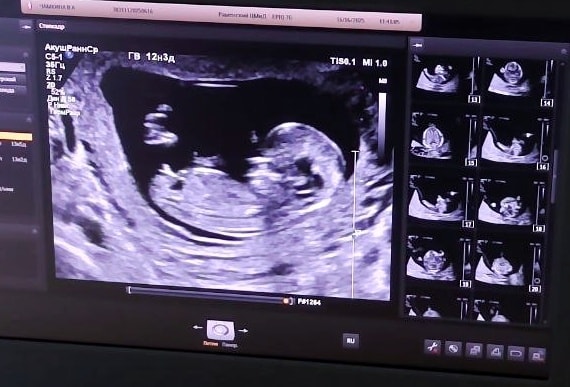

Ложусь на кушетку, с замиранием сердца жду слова доктора. ТВП - 1.6, нос прекрасно визуализируется и в целом, все замечательно. Я была на седьмом небе от счастья. Нипт ниптом, но когда видишь вживую, тогда уже отпускает окончательно. Потом врач спросила - говорить ли пол. Ответила, что я делала Нипт и уже знаю. Она все таки сказала, что тут явно мальчик)) Было удивительно, так как не часто доктор может на 12-13 неделях с уверенностью сказать.

Позвали мужа, он сделал фотку на память)) Показали ему ручки, ножки и сердечко. Пока муж стоял и смотрел на экран, я смотрела на его улыбку))) В общем, все прошло прекрасно))